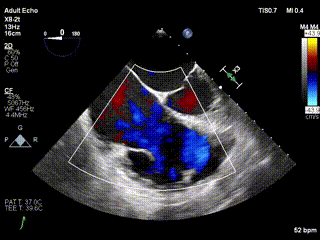

2021年12月24日,復(fù)旦大學(xué)附屬中山醫(yī)院葛均波院士團(tuán)隊(duì)成功應(yīng)用LuX-Valve Plus為一例極重度三尖瓣反流(TR)合并房顫、房缺的患者完成了經(jīng)血管三尖瓣置換術(shù),這是在前基礎(chǔ)上,本周完成的第三例經(jīng)血管三尖瓣置換手術(shù),葛均波院士、周達(dá)新教授等與心外科魏來(lái)教授、賴顥教授,心超室的潘翠珍教授、李偉教授及麻醉科的郭克芳教授共同完成了本周手術(shù),均獲得圓滿成功!患者術(shù)后超聲顯示無(wú)TR,臨床癥狀明顯改善。本周手術(shù)的成功也為L(zhǎng)uX-Valve Plus救治性臨床研究添上了濃墨重彩的一筆。

三例患者入院后,葛均波院士團(tuán)隊(duì)周達(dá)新教授、潘文志教授、張?jiān)床┦?、陳莎莎博士及心超室的潘翠珍教授、李偉教?/strong>對(duì)患者的情況進(jìn)行詳細(xì)評(píng)估和討論,最終決定為三例患者選擇LuX-Valve Plus40mm、50mm和50mm型號(hào)的瓣膜進(jìn)行手術(shù)治療。手術(shù)后即刻拔除氣管插管,術(shù)后患者三尖瓣反流癥狀得到顯著改善,復(fù)查心超結(jié)果顯示人工三尖瓣瓣膜支架固定穩(wěn)定,瓣葉關(guān)閉形態(tài)未見(jiàn)異常,未見(jiàn)明顯反流。